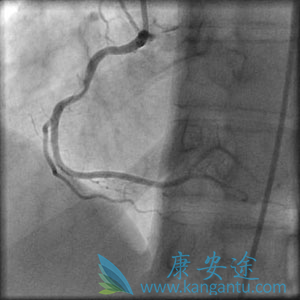

在心脏病发作(标签和箭头)和右侧,在“主要”血管成形术和支架之后阻塞血液超过阻塞的左前降支动脉,血管外流动性好

稳定性心绞痛的选择性或常规程序 - 右冠状动脉狭窄在....................之前显示,然后在支架插入后